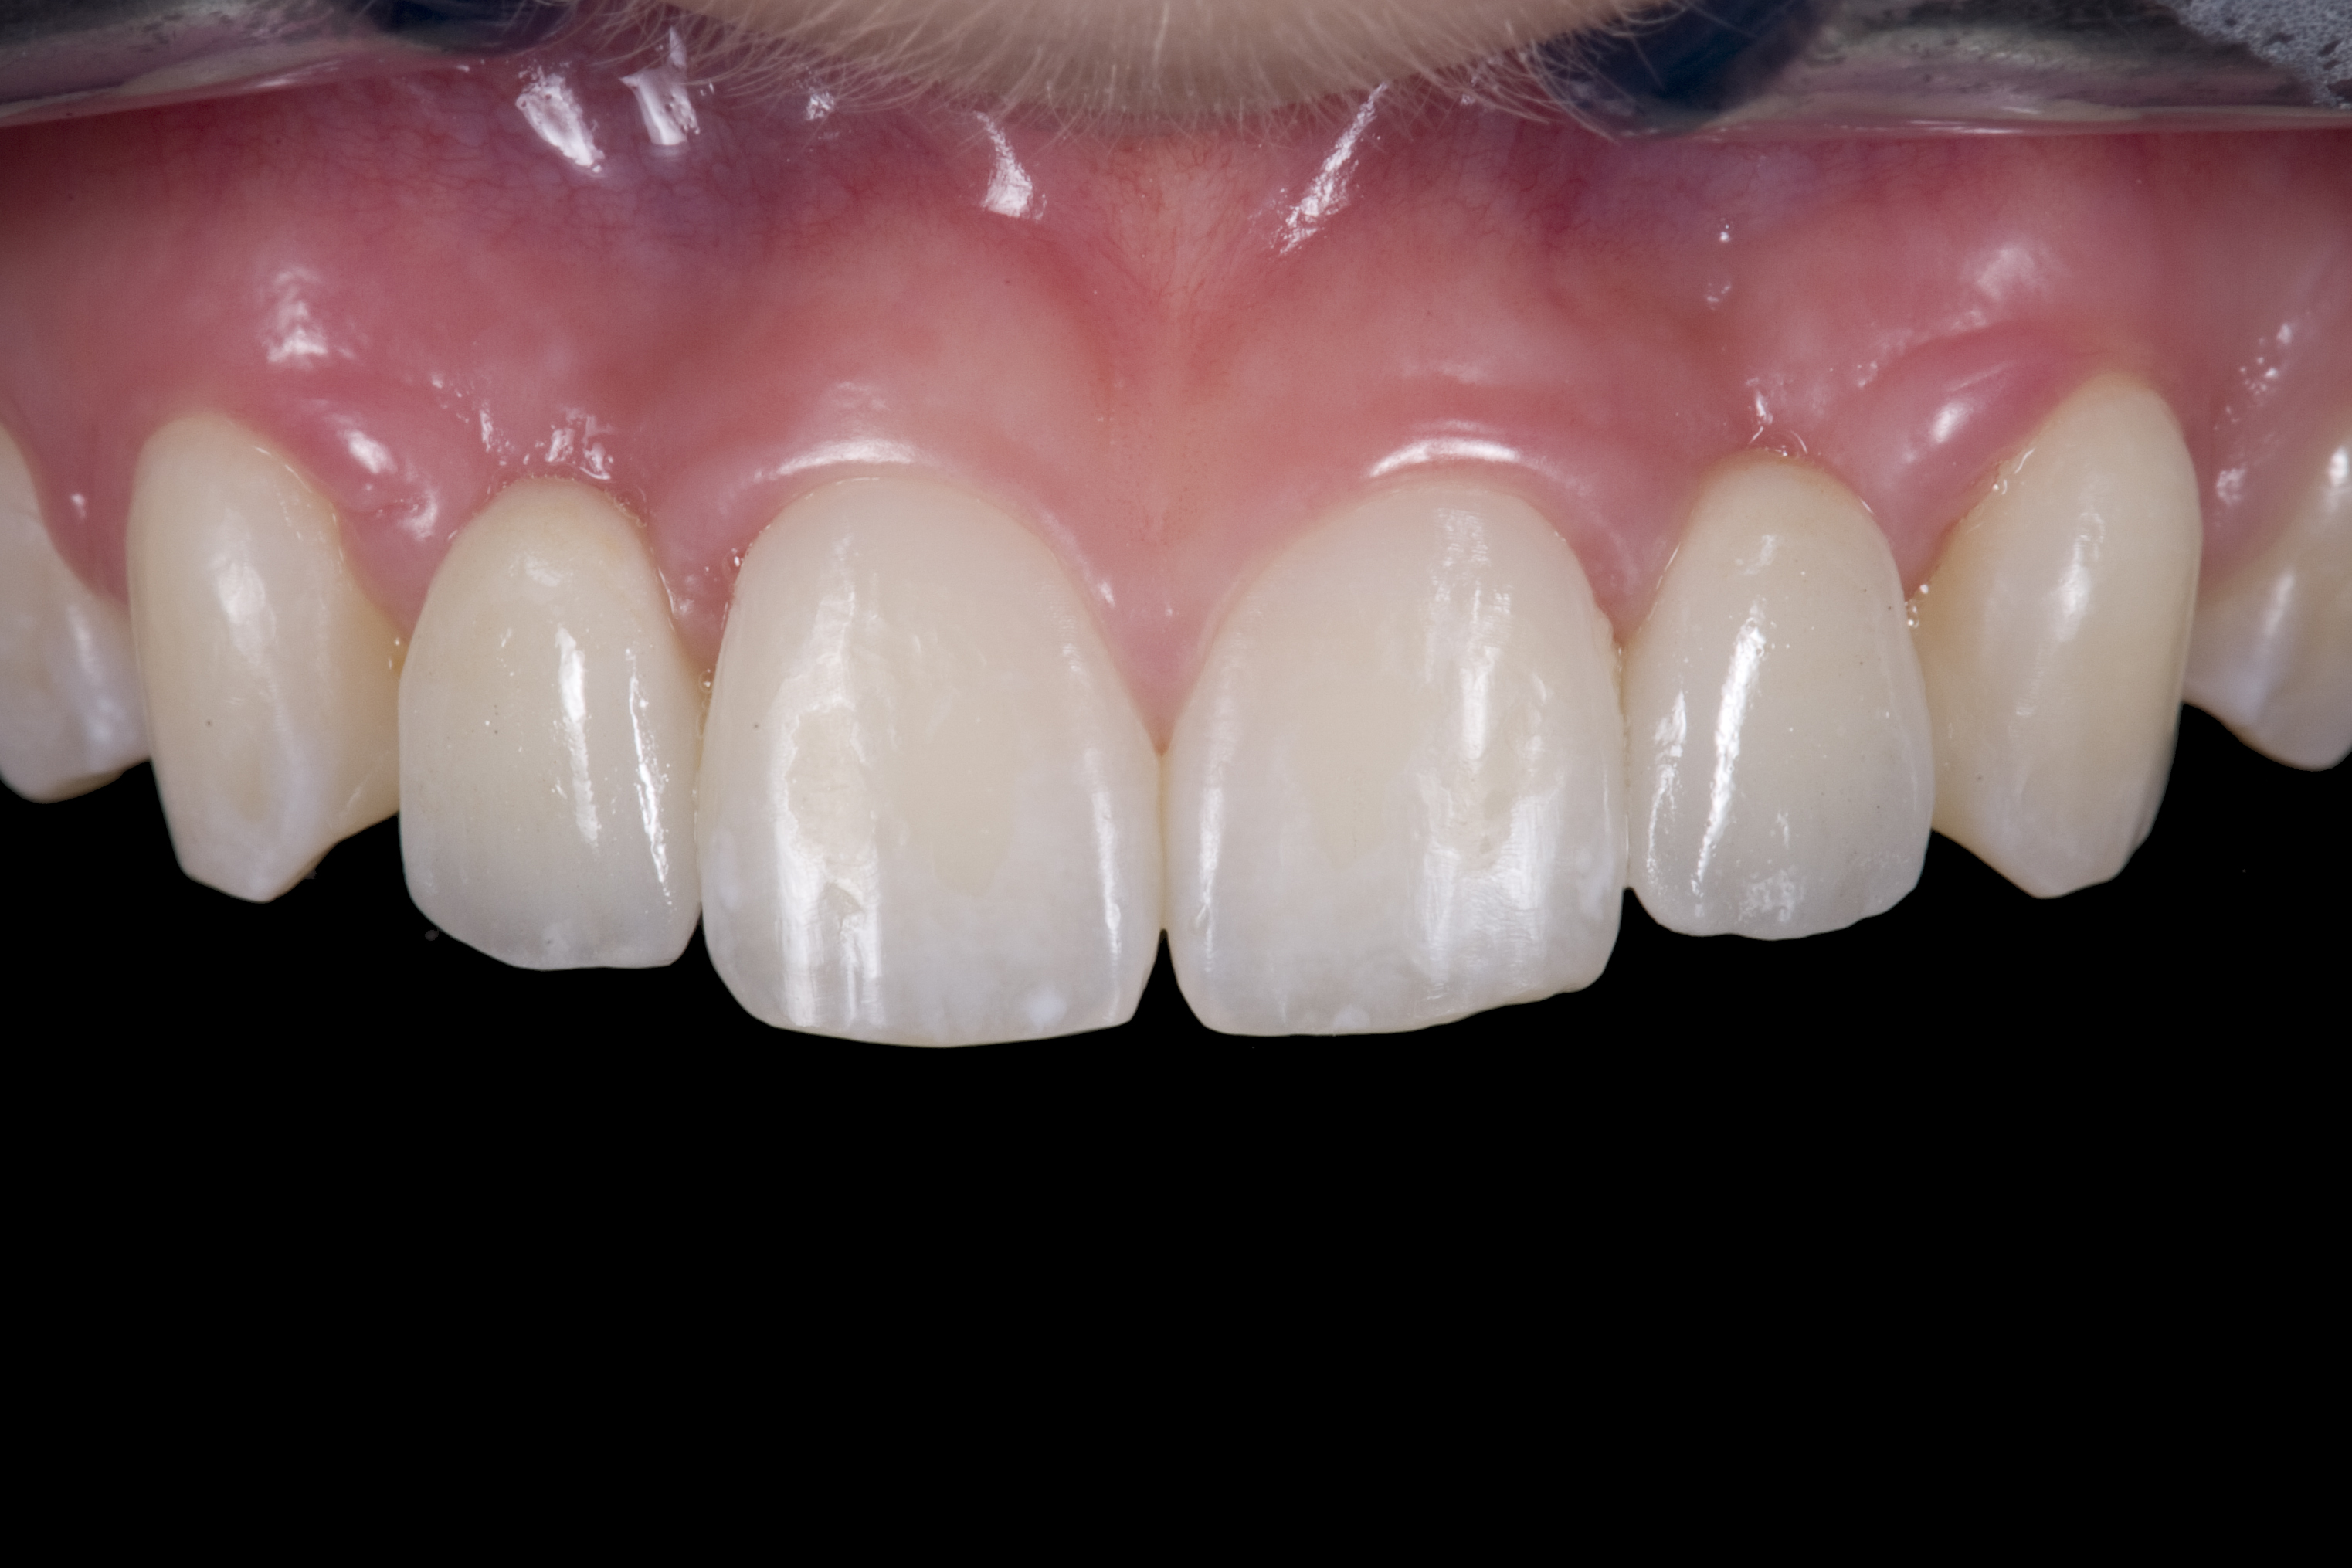

(20.) Facial view of final single-wing, modified zirconia resin-bonded bridges.

Figure 20

(21.) Smile view.

Figure 21

(22.) Right lateral view.

Figure 22

(23.) Left lateral view.

Figure 23

(24.) Occlusal view.

Figure 24

When the patient returned, the fit was evaluated in the mouth. Once verified, the internal surface of the framework was etched with a 9.5% hydrofluoric acid for 90 seconds and then salinized. After etching the enamel surface with phosphoric acid for 30 seconds and applying the primer (Single Bond Plus, 3M ESPE) to both the internal surface of the framework and the enamel, the zirconia bridge was bonded with a dual-cure resin cement (RelyX™ ARC, 3M ESPE). After the procedure, the patient ended up with a long-term, high-strength esthetic restoration advantaged by the bonding potential of fledspathic ceramic (Figure 20 through Figure 24). Six years after placement, the prosthesis had remained in place with no complications.